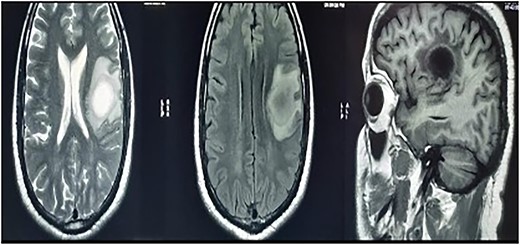

MRI brain with contrast revealed a heterogeneous irregular rim of an enhancing lesion with a size of 3.6 × 3.4 × 2.4 cm appearing in the left frontal subcortical region, with mild perilesional edema extending into the corona radiata and external capsule (Fig. 1). Due to an increased intracranial pressure, there was a mild midline shift of 5.3 mm toward the right side. Moreover, there was no evidence of intralesional hemorrhage or calcification seen.

MRI brain with contrast—a heterogeneous irregular rim of an enhancing lesion with a size of 3.6 × 3.4 × 2.4 cm appearing in the left frontal subcortical region, with mild perilesional edema extending into the corona radiata and external capsule.